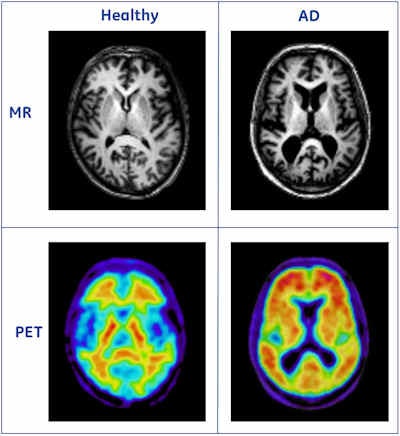

![Upper row shows MR images from a healthy person and a patient with Alzheimer's disease (AD). The right image shows clear signs of atrophy. The lower row shows PET images acquired with the amyloid imaging agent [F18]flutemetamol. The left image shows low uptake in the cortical regions, indicating no presence of amyloid plaques, while the right image shows high uptake in the cortical regions. The information from these modalities is complementary; the PET image shows information related to the underlying AD pathology, whereas the MR image shows information related to neuronal loss, a downstream effect of the disease. [F18]flutemetamol is a compound under development, and the data are from the Phase II trial). Image courtesy of Lennart Thurfjell, PhD.](https://img.auntminnieeurope.com/files/base/smg/all/image/2011/06/ame.2011_06_17_08_36_33_774_2011_06_17_predictAD_scans.png?auto=format%2Ccompress&fit=max&q=70&w=400)

To meet this need, the PredictAD team has developed tools for measuring the size of the hippocampus, the atrophy rate of the hippocampus, and two approaches based on comparing patient data with previously diagnosed cases available in large databases. PET is also being studied in the project. A novel tracer developed recently especially for diagnostics of Alzheimer's disease provides promises for very early diagnosis of the disease.